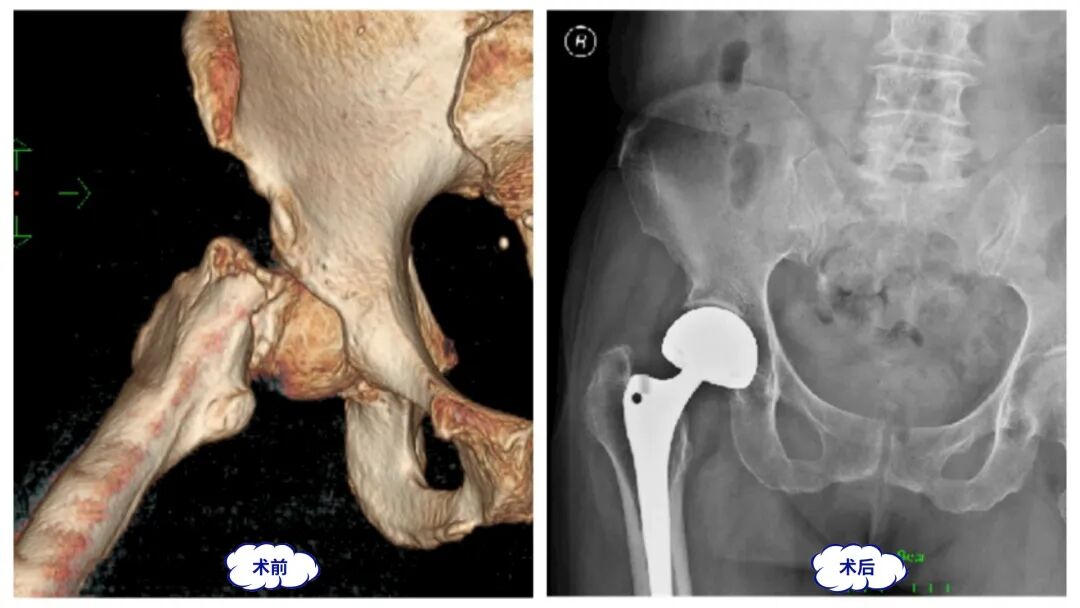

关节专业